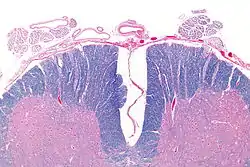

| Аксіальний розріз спинного мозку спереду, який показує передню спинномозкову артерію (верхньо-серединне положення). | |

| 1: Задня спинномозкова вена 2: Передня спинномозкова вена 3:Задньолатеральна спинномозкова вена 4: Сегментарна спинномозкова вена 5: Задня спинномозкова артерія 6: Передня спинномозкова артерія 7: Сегментарні спинномозкові артерії | |